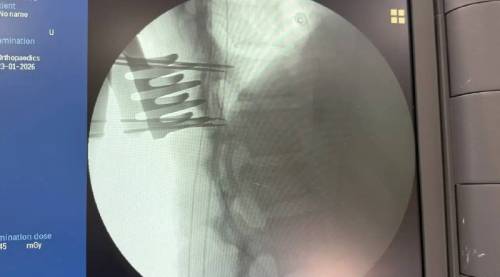

19 января во Владивостокскую клиническую больницу №2 из Арсеньева была экстренно доставлена молодая девушка с тяжёлой травмой — компрессионным переломом позвонка со стенозом позвоночного канала. Перелом сопровождался сдавливанием спинного мозга, что привело к парезу ног и нарушению функций тазовых органов.

После предоперационной подготовки нейрохирурги провели сложную четырёхчасовую операцию. Врачи устранили компрессию спинного мозга и стабилизировали позвоночник металлоконструкцией, предотвратив риск необратимых последствий. «Ключевую роль сыграло именно оперативное вмешательство. Мы сняли давление со спинного мозга и уже на вторые сутки начали раннюю реабилитацию», — отметил заведующий 1-м нейрохирургическим отделением Дмитрий Захаров.